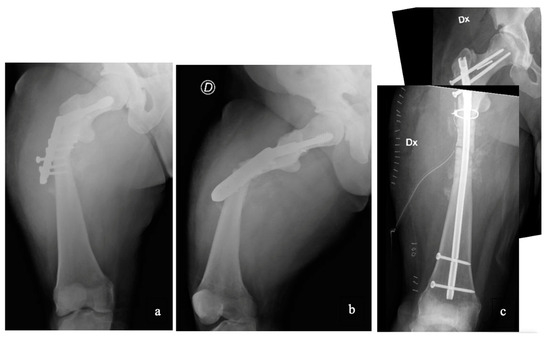

Case 3 had a displaced tibia shaft fracture as a consequence of a low-energy trauma that occurred during pediatric age. We initially planned to synthesize the fracture with elastic intramedullary stable nailing (ESIN), as it was deemed a less invasive surgery in view of the patient’s age. However, during surgery, we experienced several difficulties from the beginning. These occurred first throughout the preparation of the entrance of the elastic nail due to the extreme thickness of the cortical and, second, in an attempt to advance the nail along the basically inexistent canal. Therefore, we found ourselves forced to change the ongoing approach by then proceeding with an open reduction and plate fixation. Although we completed the surgery with a satisfying result, we faced a few difficulties. During the drilling, in fact, the feeling of the bone was as if managing marble, to the extent that we risked drill breakage on a number of occasions (Figure 2). Fortunately, the fracture healed on time, and there were no complications at the follow up.

Figure 2. Case 3 had a displaced tibia shaft fracture that we initially planned to synthesize with two elastic titanium nails. However, during surgery, we experienced several difficulties throughout the preparation of the entrance of the elastic nail (circle) and then also in an attempt to advance the nail along the canal. Therefore, we proceeded with an open reduction and plate fixation.